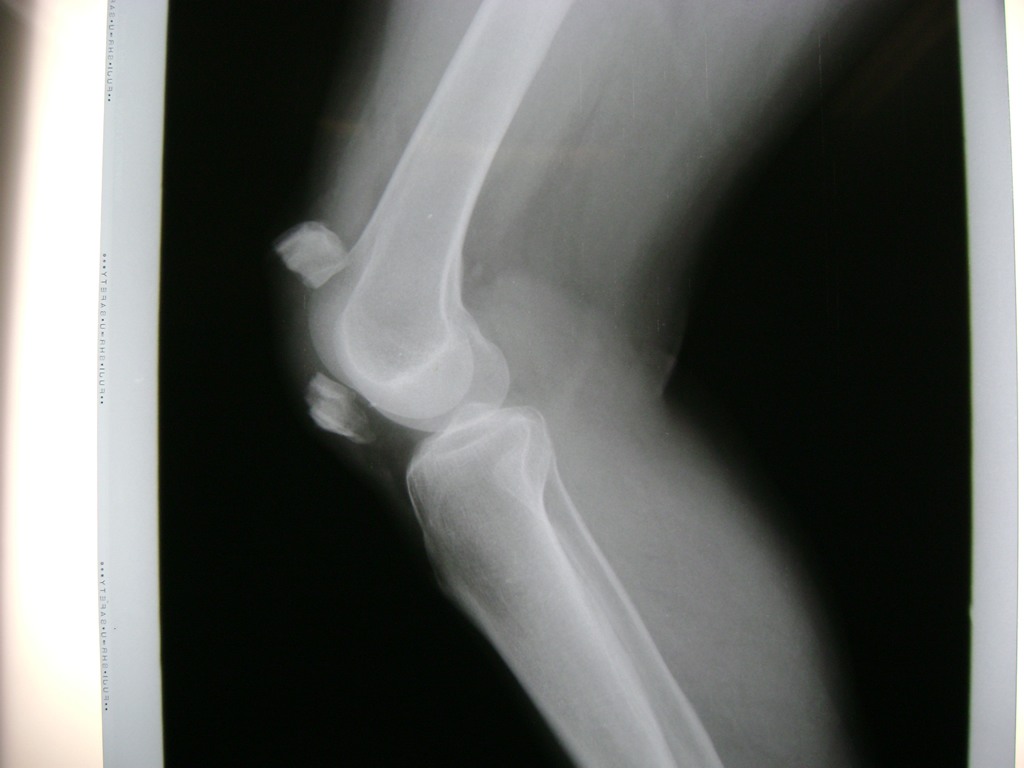

Cirugía de Fémur - Rodilla